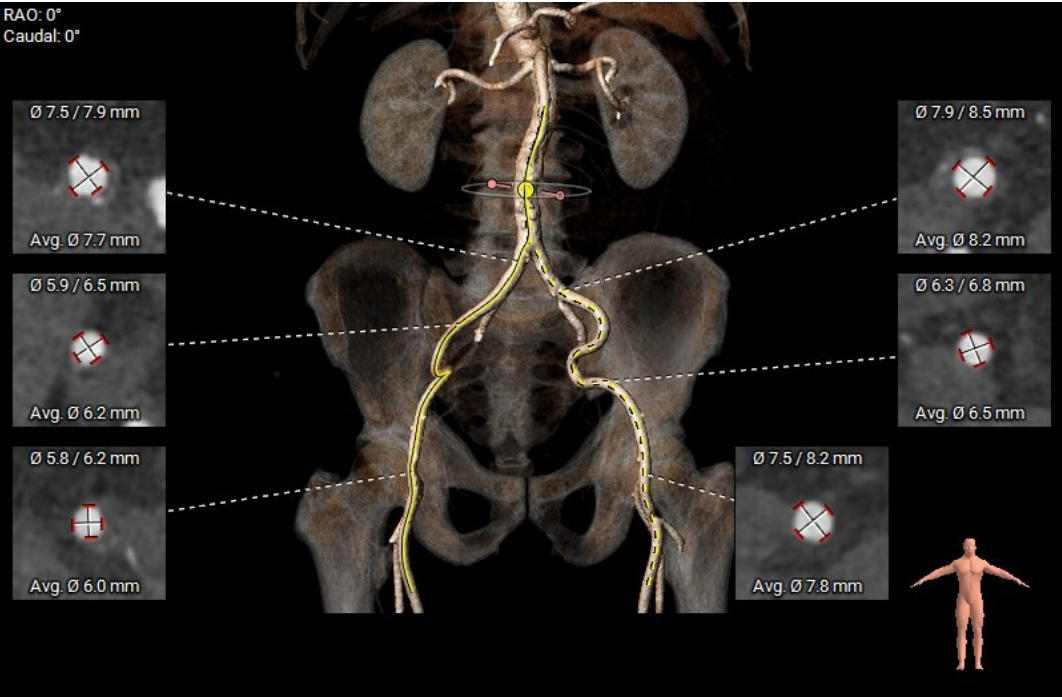

3.该患者股动脉内径偏小,轻度迂曲。

此患者的股动脉内径最窄处仅有6.2mm,VitaFlow Liberty™的自带内联鞘系统可降低对血管内径的要求,使装载了瓣膜的输送系统能够顺滑的通过股动脉,降低血管并发症的风险。